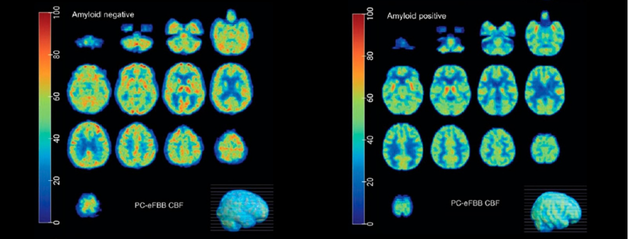

Using Brain Imaging to Measure Cerebral Blood Flow in Patients with Cognitive Impairment

Helena and Moss's Visualization of Brain Perfusion